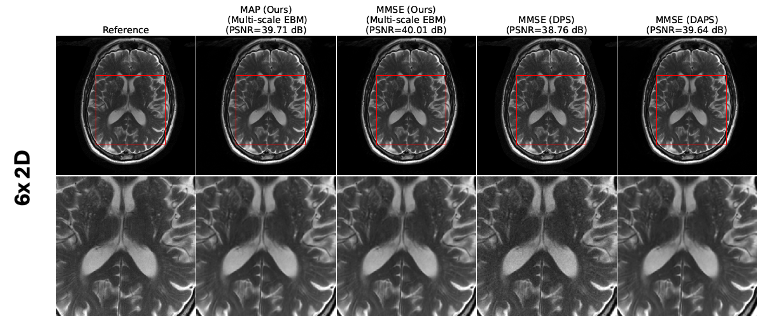

4.2.2 MRI image reconstruction

We evaluate multi-scale EBMs for MRI reconstruction from undersampled measurements at two acceleration factors. EBMs were distilled from the diffusion model in [1] using a T2-weighted brain dataset of 40,442 slices and tested on 40 slices. We compare against two diffusion-based algorithms: (a) DPS and (b) DAPS. We use the same noise scheduler as in the previous example (, , ), Langevin steps, and iterations. MMSE and uncertainty are estimated from five samples; MAP is computed via Algorithm 1 over iterations. Table 3 shows EBMs achieve performance comparable to DAPS for both accelerations. Fig. 4(a,b) illustrates reconstructions at 4× and 8×. Unlike diffusion models, EBMs provide MAP estimates without multiple samples, reducing inference cost and enabling practical clinical deployment.

While the table focuses on reconstruction quality, it is important to note that ALPS achieves these results with fewer function evaluations compared to DAPS. This efficiency stems from ALPS’s smoother trajectory from initialization to posterior, reducing the need for excessive annealing steps and iterations. Fig. 9 shows the MAP estimate and posterior sample generated via ALPS algorithm for different inverse problem. We also show the MRI reconstructions at different accelerations in Fig. 10. Fig. 11 shows the three different estimates that are given by the EBM: MAP, MMSE, and the uncertainty estimates for three different accelerations. One can observe that as the acceleration increases, the uncertainty of the reconstruction also increases. We also report the average NLPr and negative log-posterior (NLPo) values of the generated samples across different accelerations in Table 5. One can observe that as the acceleration increases, the mean NLPr and mean NLPo values decrease. This occurs because higher acceleration leads to more severe undersampling, making the reconstruction problem increasingly ill-posed. In such settings, the ALPS algorithm relies more heavily on the energy model. As a result, the algorithm outputs reconstructions with lower prior energies, and the posterior energies follow the same trend due to the reduced influence of the negative log-likelihood term.